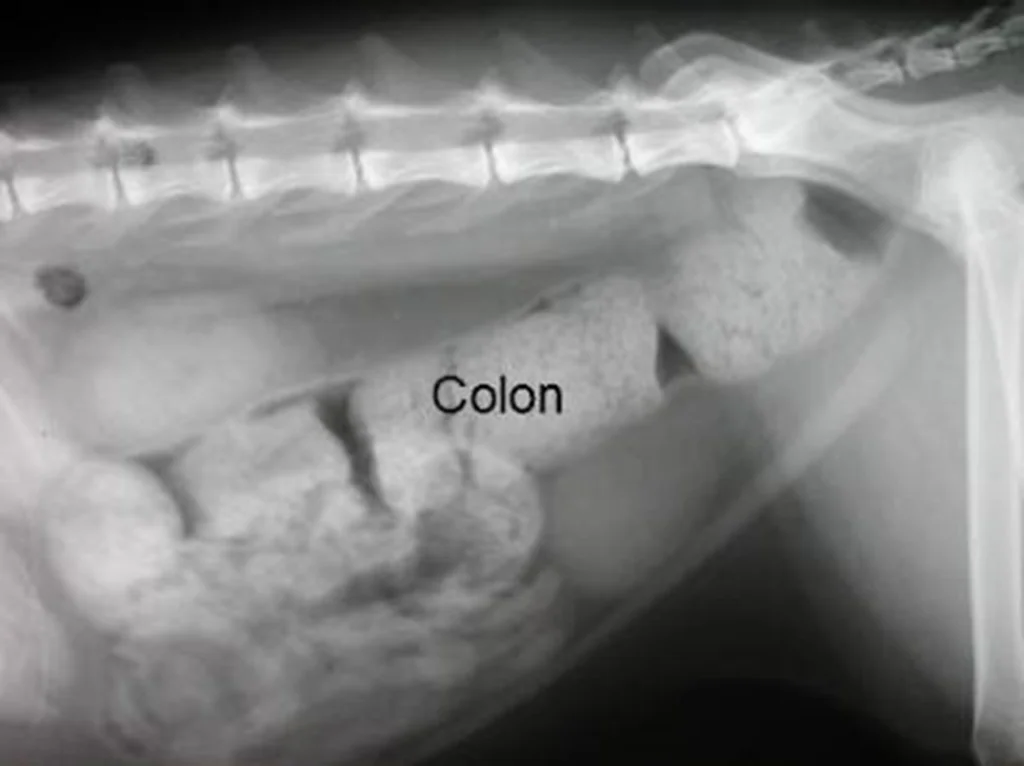

O exame radiográfico pode ser de grande valor diagnóstico, não só na confirmação da constipação e do megacólon, como na identificação de possíveis fatores relacionados a causa da constipação, p.e., fraturas antigas de coxal com estreitamento do canal pélvico, lesões degenerativas em coluna lombo-sacral ou sacro-coccígea.

O megacólon é confirmado quando o exame radiográfico, em projeção lateral, evidencia um cólon com diâmetro 1,5 vezes maior que o tamanho da sétima vértebra lombar.

Para tanto, a abordagem terapêutica desses pacientes depende da gravidade e grau de constipação. A imagem a seguir, ilustra a conduta escolhida, de acordo com a intensidade ou dificuldade que o gato encontra para evacuar.

Didaticamente, vamos classificar a constipação em três graus, leve, moderada e grave. As condutas empregadas para cada paciente, estarão diretamente relacionadas ao grau de constipação apresentado.